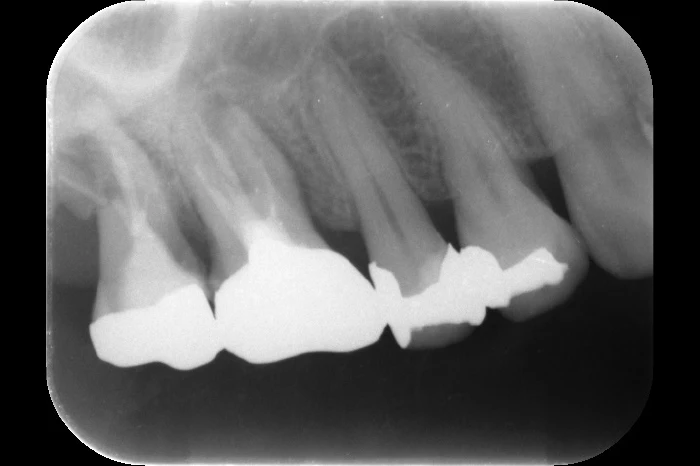

実際にあったケース

ある患者さんが「噛むと痛くて何も食べられない」という主訴で来院されました。

数日間、流動食しか摂れない状態でした。

レントゲンを撮影すると、歯の根が横方向に折れている状態(破折)が確認されました。

原因は「就寝中の歯ぎしり」

患者さんに経過を伺うと、「寝て起きたら急に痛くて噛めなくなった」とのことでした。

つまり、寝ている間の歯ぎしり・食いしばりで歯が折れた可能性が高いと考えられます。

その結果、歯にヒビが入り(マイクロクラック)、それが進行して最終的に破折するという流れが起こります。